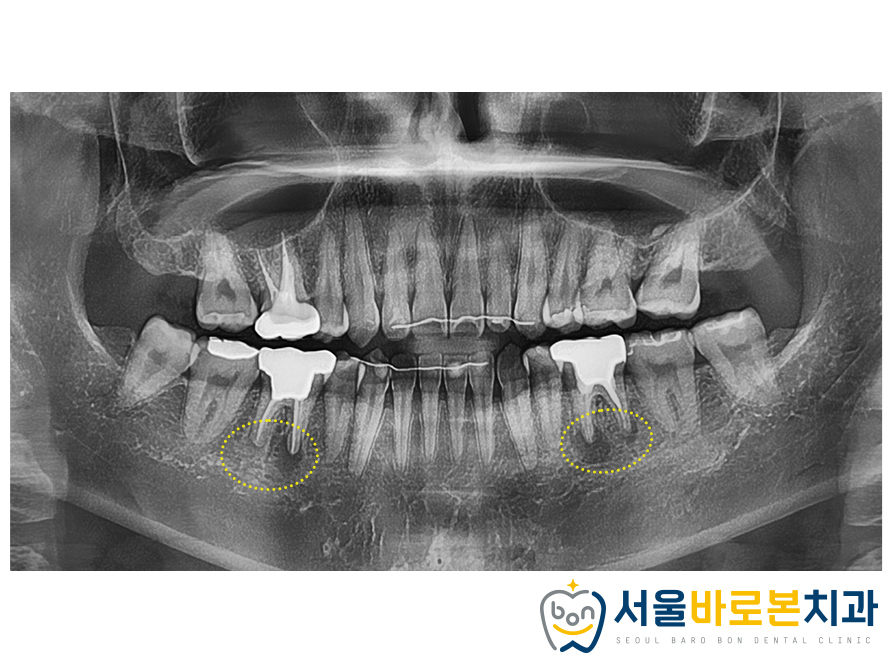

양측 모두 합쳐서

약 1개월 정도 치료기간이 소요되었으며

잘 마무리 해드렸습니다.

재신경치료를 진행하고나면

엑스레이 사진을 통해

염증부위를 관찰하게 되는데요.

1개월 후 사진 보시면

처음에 비해 염증이 줄어들고

약재들이 잘 자리하고 있는 것을

확인하실 수 있습니다. 🤗